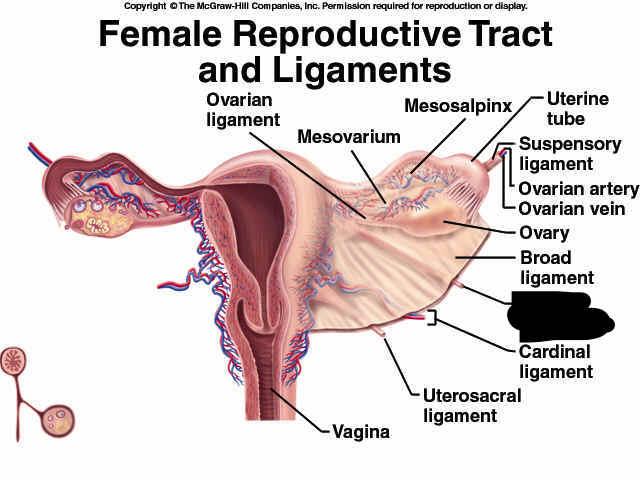

Broad ligament

Cervix

Clitoris

Endometrium

Fimbriae

Gonadal (=testicular/ovarian) artery/vein

Labia majora/minora

Myometrium

Overian ligament

Ovary

Perimetrium

Prepuce (=clitoral hood)

Round ligament (of uterus)

Uterine (=fallopian) tube

Uterus

Vagina

Vaginal orifice